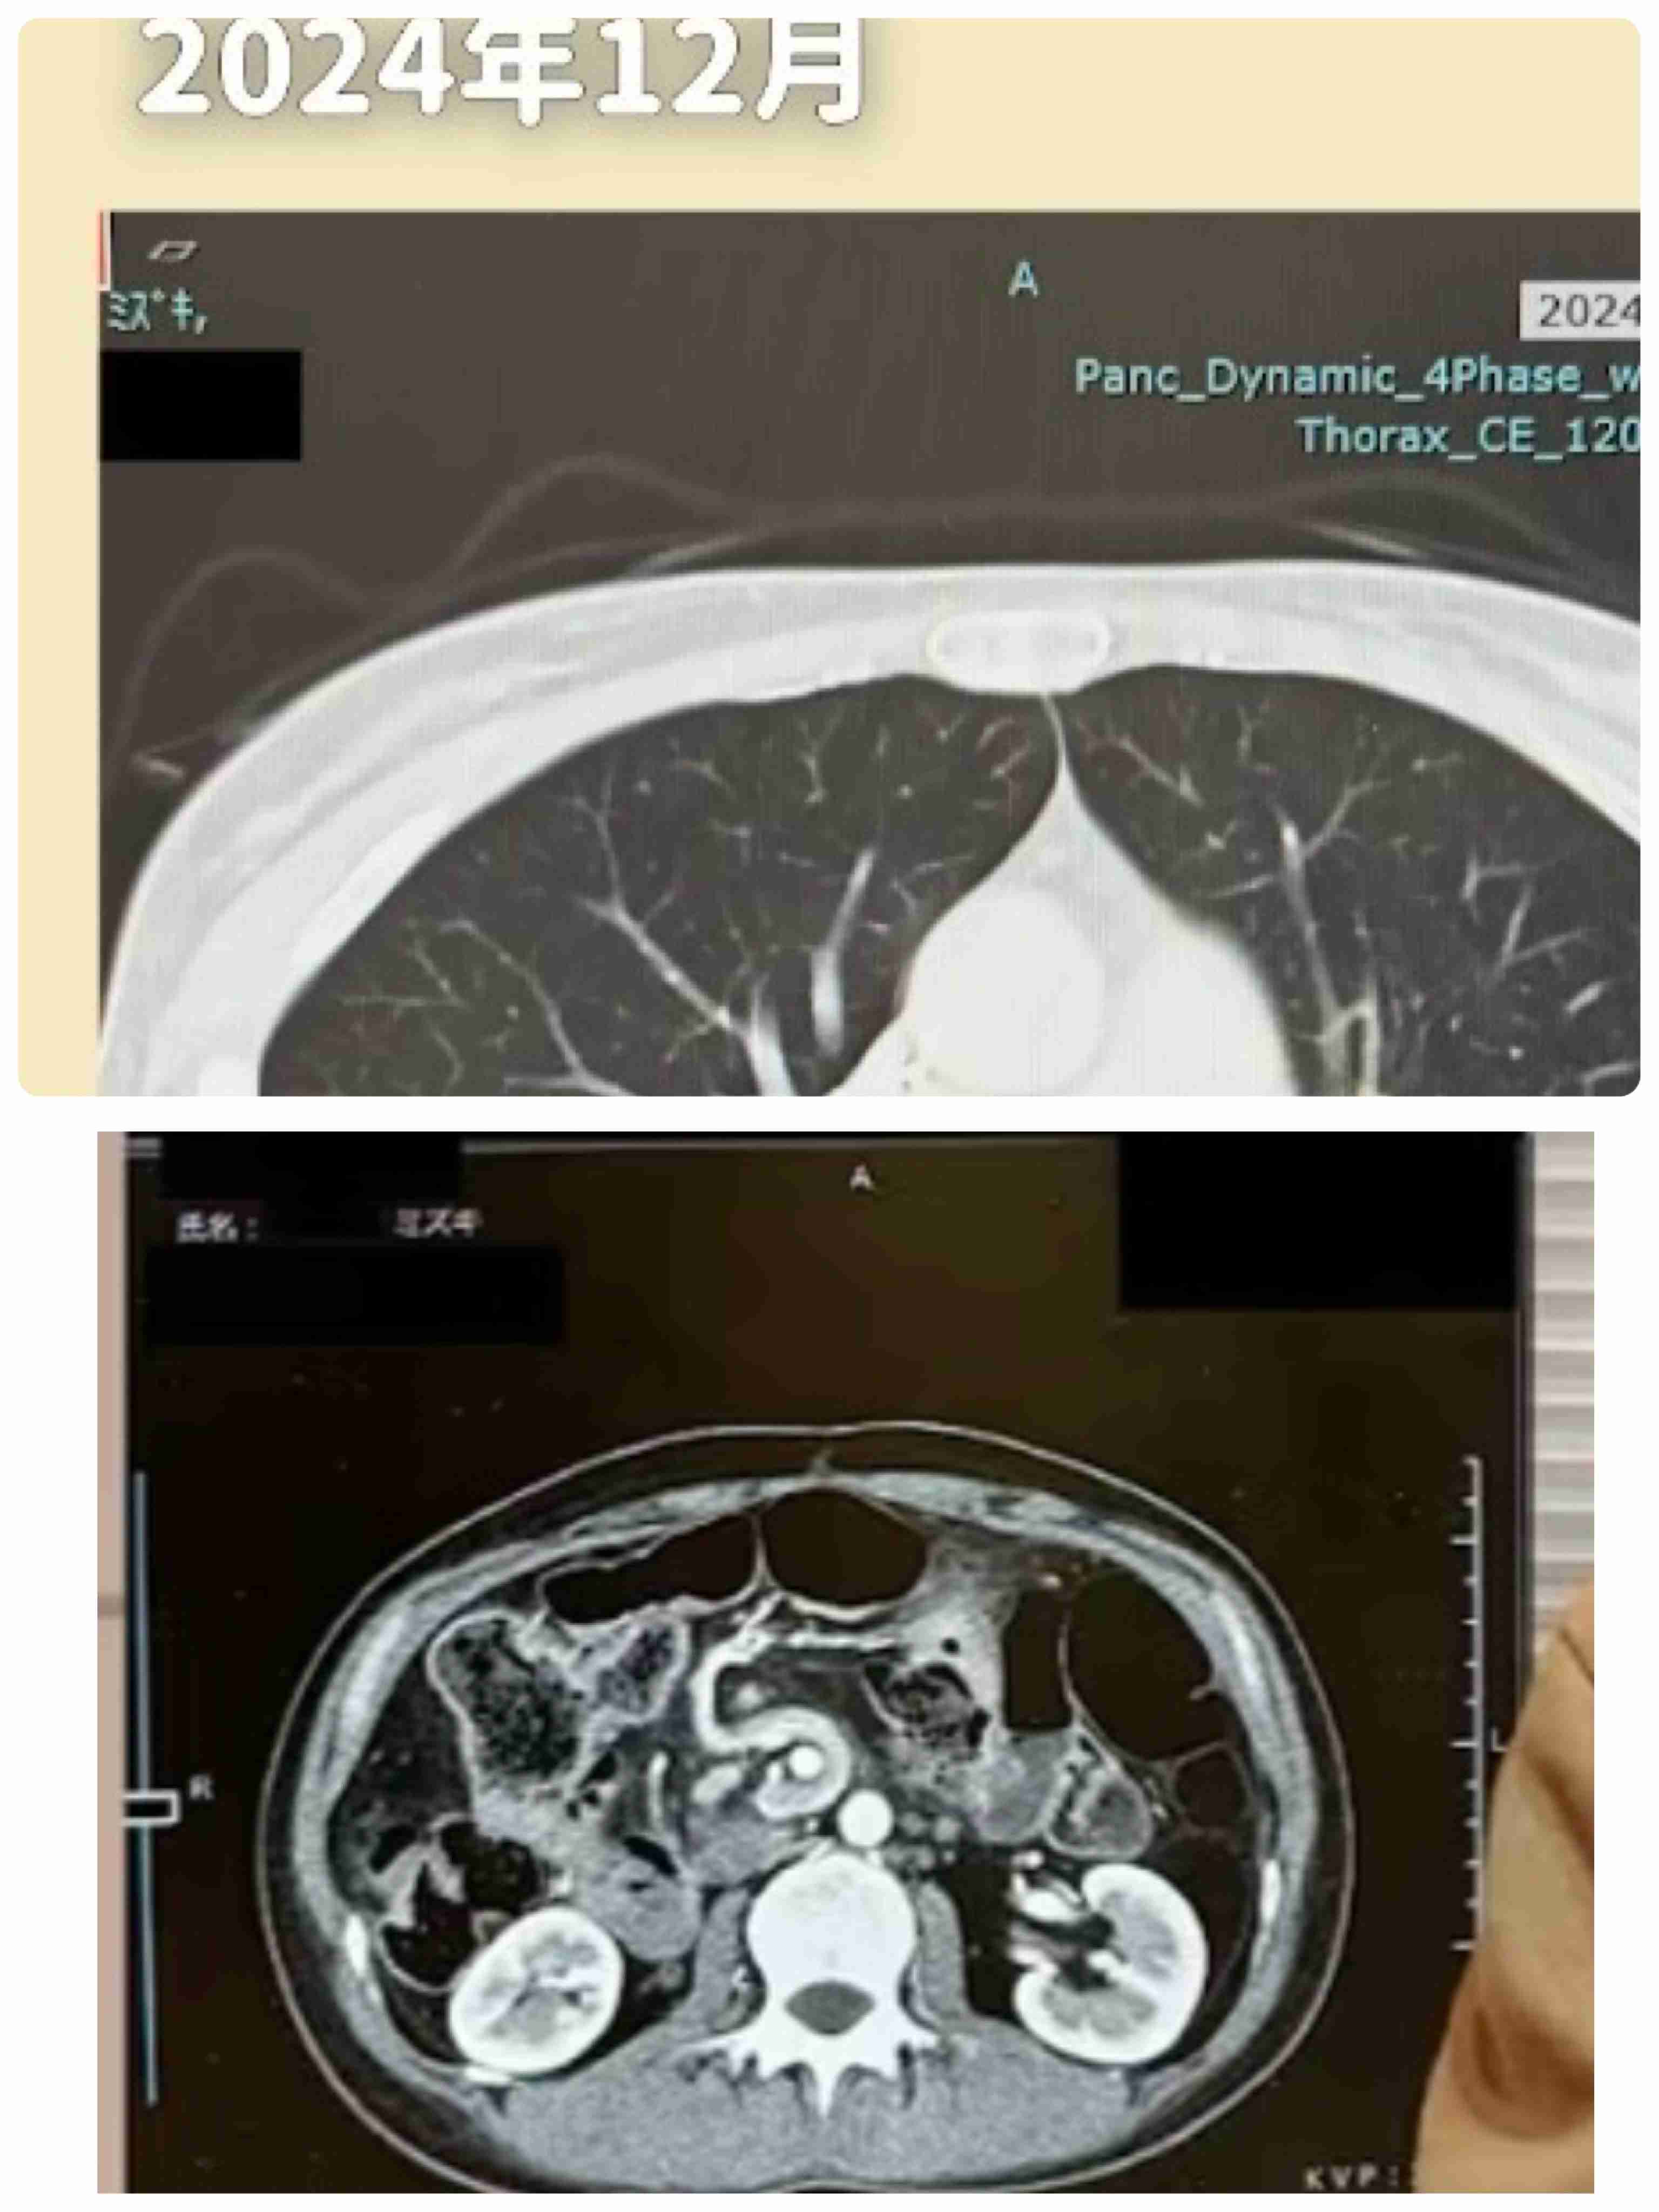

CTを撮るたびに背骨の形がかわる奇跡返信

-1

今回の動画は特にそれが顕著だったと思う。+52